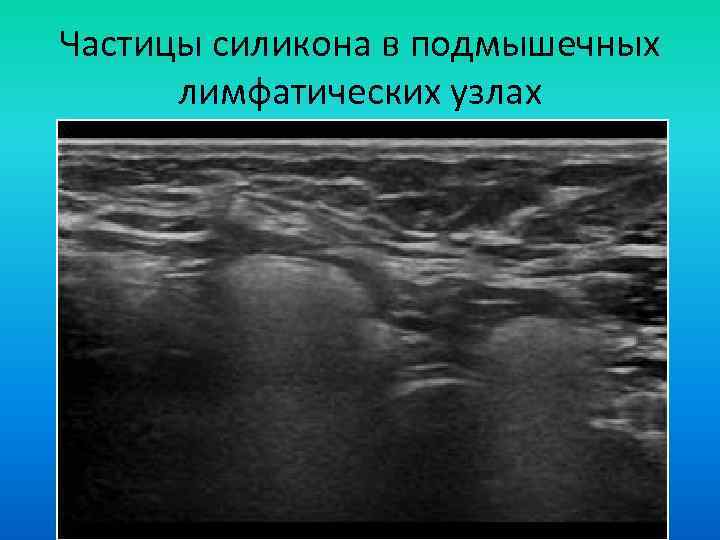

Частицы силикона в подмышечных лимфатических узлах Частицы силикона в подмышечных лимфатических узлах